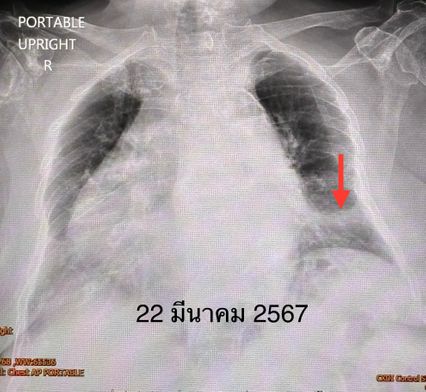

ผู้ป่วยให้ประวัติว่า เป็นโรคหอบหืด ความดัน ไขมัน เบาหวาน กระดูกพรุน อยู่บ้านเดินไม่ได้ ช่วยตัวเองไม่ได้ นอนติดเตียง แต่ผู้ป่วยรู้ตัวดี กินอาหารได้ทางปาก ไม่ดื่มเหล้า ไม่สูบบุหรี่ เข้านอนรักษาในโรงพยาบาล เมื่อวันที่ 22 มี.ค.67 แพทย์ตรวจร่างกาย ไม่มีไข้ ระดับออกซิเจน 95% ฟังปอดมีเสียงครืดคราดทั้ง 2 ข้าง เจาะเลือด พบว่าเม็ดเลือดขาวในเลือดสูง 17,070 เอกซเรย์ปอดมีฝ้าขาวที่ปอดซ้ายด้านล่าง แยงจมูกส่งตรวจรหัสพันธุกรรม 22 สายพันธุ์พบเชื้อ Rhinovirus

แพทย์วินิจฉัยว่า ปอดอักเสบจากการติดเชื้อ Rhinovirus อาจมีเชื้อแบคทีเรียอย่างอื่นมาแทรกทำให้เม็ดเลือดขาวขึ้นสูง รักษาด้วยการให้ยาเสตียรอยด์ขนาดต่ำ และยาปฏิชีวนะ Ceftriaxone ทางเส้นเลือดร่วมด้วย 5 วัน เพาะเชื้อแบคทีเรียในเลือดไม่ขึ้น คนไข้ดีขึ้น ไม่มีไข้ ไอลดลง เหนื่อยน้อยลง เม็ดเลือดขาวลดลงเหลือ 9,240 เอกซเรย์ปอดฝ้าขาวที่ปอดซ้ายด้านล่างหายไป แพทย์อนุญาตให้กลับบ้านได้